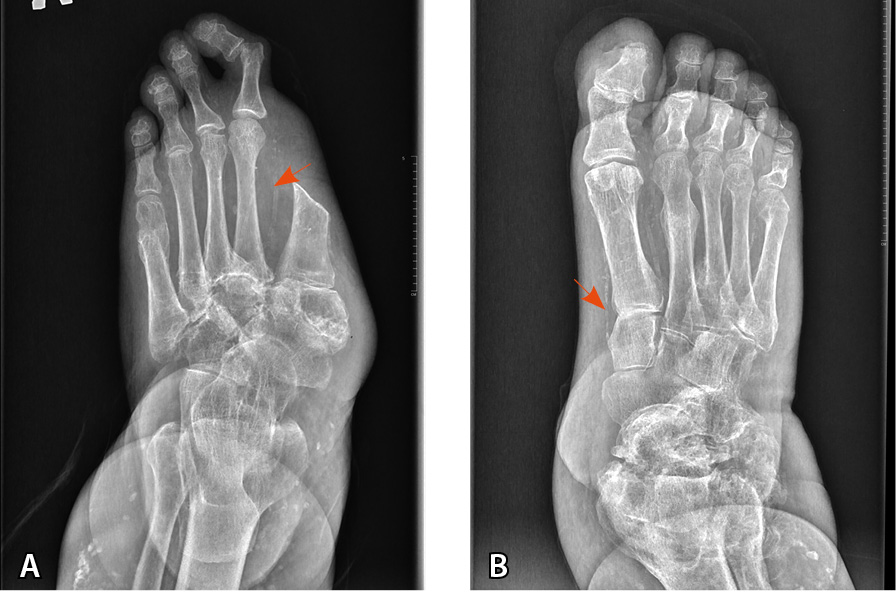

В 2003 г. травма правого голеностопного сустава, диагностирован лодыжечный перелом, обусловленный ДНОАП, наложена индивидуальная иммобилизирующая повязка Total Contact Cast, которую пациент носил в течение 6 месяцев. В 2009 г. травма левой стопы с формированием нейропатической язвы, диагностирована подострая стадия ДНОАП. В 2017 г. парциальная резекция пролабирующей кубовидной кости слева. В 2020 г. ампутация I пальца левой стопы с резекцией головки I плюсневой кости по поводу остеомиелита (рис. 2, 3).

Рис. 3. Рентгенограмма обеих стоп пациента Т. в прямой проекции (стрелками указаны кальцинированные сосуды):

А – артропатическая перестройка структуры костей предплюсны, переломы на уровне оснований 3–5-й плюсневых костей с признаками консолидации. Консолидированный перелом головки 5-й плюсневой кости. Ампутация I пальца;

Б – артропатическая перестройка структуры костей предплюсны и правого голеностопного сустава, консолидированные переломы II, III, V пальцев. Остеомиелит ногтевой фаланги I пальца